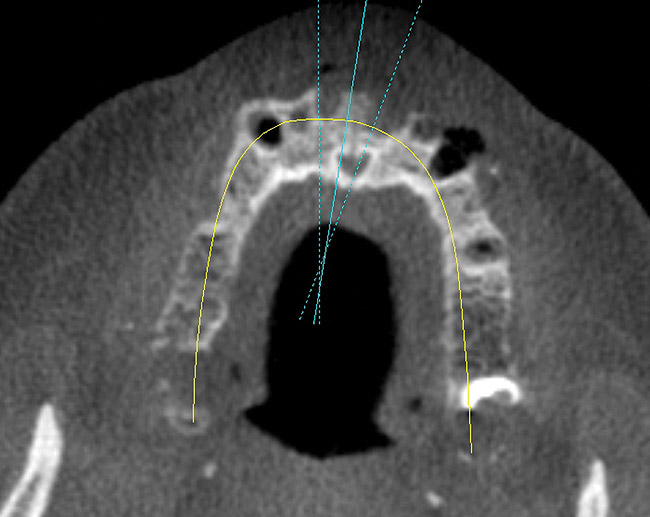

Understanding the drugs that a patient is currently taking, allergies, and previous notable medical problems are important to the treatment planning process. Dialogue with the patient in reference to treatment options and alternatives is another important component to treatment planning for a graft. A discussion of which materials will be used for the graft and its safety is also an important step. It is the author’s opinion that a cone beam computed tomography (CBCT) scan should be obtained before grafting. A CBCT scan offers unparalleled visual information that allows a surgeon to plan correctly for volume of graft material, visualization of anatomical parameters, and coordination of the prosthetic end result in relation to the graft.15

An interactive CBCT scan offers a 3D view that allows visualization of a ridge defect with lifelike reality. In the maxillary arch, a CBCT scan shows the anatomy of the maxillary sinus with regard to pathology and available bone for dental implant placement. In the mandible, the inferior alveolar nerve can be traced and measured. A CBCT scan also shows the density of surrounding bone before grafting. This can indicate a need for grafting for improved mineralization and volume. A CBCT scan also offers the advantage of reduced radiation exposure over a fan-beam traditional CT scan.

Other advantages of a CBCT scan are the in-office availability, expedient results, and interactive format. Through using one of the many interactive CBCT programs available, bone density, volume measurements, virtual implant placement, and 3D volumetric visualization can be obtained.16

A 53-year-old woman in good health presented for the replacement of missing teeth on the maxillary arch and periodontal therapy of the mandibular arch. A CBCT scan was taken that revealed the need for bone grafting on the maxillary ridge and maxillary sinus areas in the panographic (Figure 14) and axial (Figure 15) views. Bone loss was noted on the facial plate areas of the anterior ridge. A treatment plan was created to graft the maxillary ridge and sinuses bilaterally, and then to place 12 dental implants to support a fixed prosthesis on the maxillary arch.The treatment plan for the mandible consisted of periodontal surgery to save her remaining teeth.

After 6 months of healing, a CBCT scan was taken and good bone formation was seen on the axial (Figure 18) and panograph (Figure 19) views. The CBCT was then used to plan for placement of dental implants (Figure 20). Upon full-thickness reflection of the ridge, abundant bone contour was observed. Internal hex dental implants (BioHorizons) were placed according to the locations planned on the CBCT (Figure 21). After a healing period of 4 months, the implants were uncovered (Figure 22) and abutments were placed (Figure 23). A panograph taken 1 year after this stage revealed the final restorations on well-integrated implants (Figure 24). The patient’s smile reveals a fixed prosthesis that simulates her natural teeth (Figure 25).